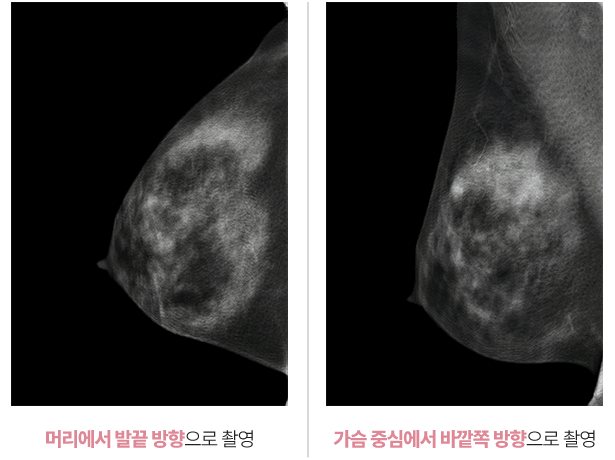

유방검사